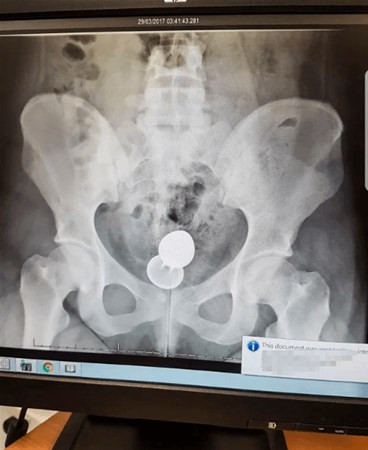

Galerinin tamamı için tıklayınızEv arkadaşı hemen doktora gitmelerini söylemesine rağmen durumdan çok utanan Emily zorla da olsa hastaneye gitmeye ikna oldu.Hastanede durumundan bahseden Emily Georgia’ya hemen gerekli tetkikler yapıldı. Çekilen röntgen filminde olayın boyutlarının çok tehlikeli olduğunu fark eden doktorlar durumu Emily’e anlattılar.